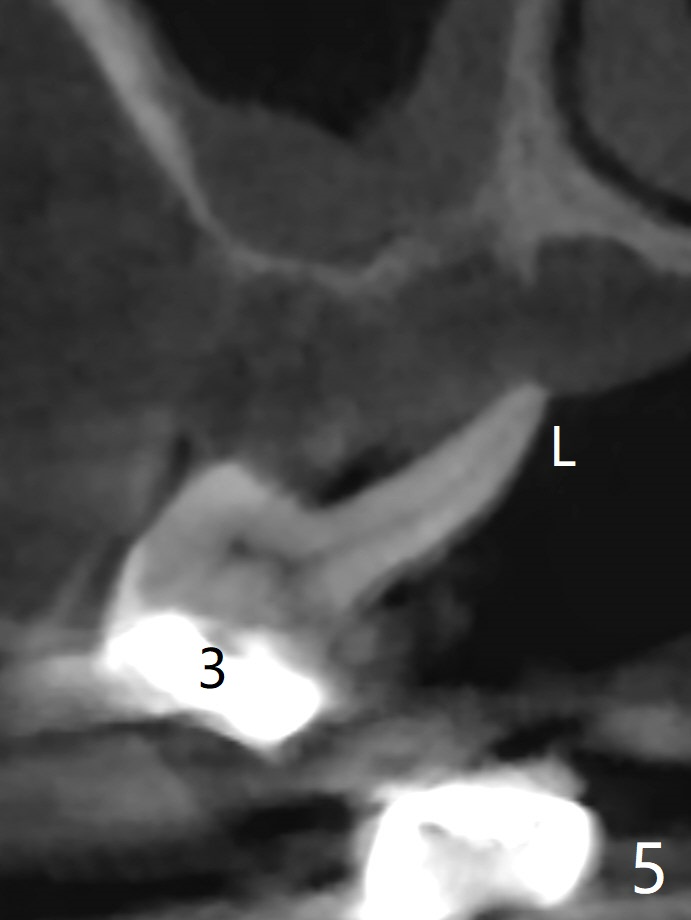

A 51-year-old woman has poor dentition with chronic periodontitis (Fig.1). She has financial constraint, but refuses RPD, insisting upon UR posterior implants first. After discussion of severe bone loss, she agrees with bone graft first (Fig.2-4). Since the bone atrophy is the most severe at #3 (Fig.5 coronal section; L: lingual), sinus lift (Fig.6 arrow) is conducted after extraction (black). Use sticky bone (Fig.7 red circles) and Titanium-reinforced Cytoplast (white) for socket preservation. Or if Magicore is able to achieve primary stability (Fig.8 green), an abutment (pink) will be placed for an immediate provisional (white). The latter are capable of holding bone graft in place. Since bone loss at #2 and 4 is less severe (Fig.9 sagittal section), their roots will act as walls to keep bone graft (Fig.11) in place after #3 extraction (Fig.10).